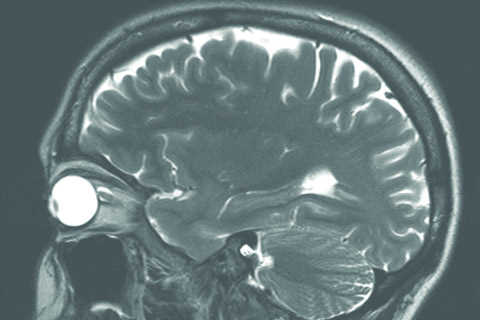

In ophthalmology, structural MRI can be useful in cases where optical imaging devices are stymied by optical pathway opacities. It may also be one of optometry’s greatest tools, particularly if a visual field defect can’t be explained based on ocular presentation alone, said US optometrist Dr Molly Ann Clymer. An MRI is warranted in cases of bilateral optic nerve disc oedema; optic nerve disc pallor unexplained by ocular history; unilateral optic nerve disc oedema with pain on eye movement, proptosis, suspicion or history of demyelination, or extraocular muscle restrictions, she said.